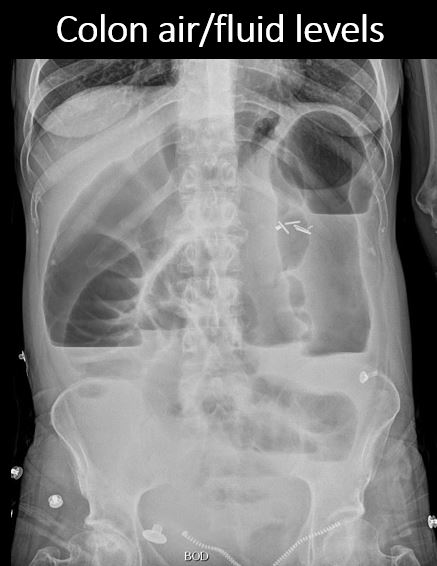

There are air/fluid levels in the colon. |

N/A | NA |

There is extraluminal air in the soft tissues of the abdomen which could be from necrotizing fasciitis. A CT scan and urgent surgical consult are recommended. There is airspace disease or atelectasis in the left lung base.

Notify the clinical team verbally and immediately about possible necrotizing fasciitis and need for urgent surgical consult.

Emergent: non-routine communication required immediately or within 30 minutes